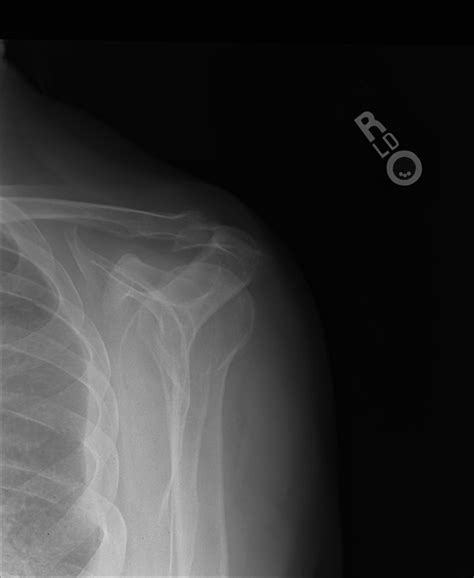

A bone spur is a bony projection that develops along bone edges. In the shoulder, bone spurs can form on the acromion (the highest point of the shoulder blade), the humerus (upper arm bone), or the clavicle (collarbone). These spurs can cause pain and limit shoulder movement, especially when they rub against tendons, ligaments, or other bones.

• Imaging Tests: Diagnostic imaging tests, such as X-rays, CT scans, or MRI scans, can help visualize the bone spur and assess the extent of the damage. These tests provide detailed images of the shoulder joint and surrounding tissues.

X-ray Uses radiation to produce images of the bones. Identify bone spurs and assess bone structure.